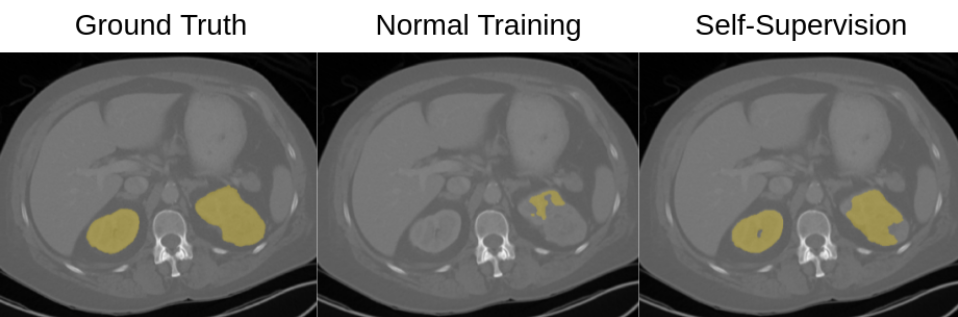

Refer to caption

Figure 5: Qualitative comparison for multi-organ segmentation in the presence of image corruption. From left to right: the original image with the ground truth segmentation, the corrupted image, the predictions from normal training, and the predictions from self-supervision.

Robustness in Segmentation: We also perform the image corruption experiments for the multi-organ segmentation task using UNet architecture. Fig. 4 describes the overall Dice score over corruption for normal training and self-supervision. Plimit-from𝑃P-values <0.001absent0.001<0.001 are reported in red, showing that brightness, contrast, Gaussian noise, and resolution yielded a statistically significant result. Fig. 4 shows that self-supervision has superior segmentation performance in the presence of data corruption. Impulse noise is the only corruption for which self-supervision has lower performance. Nevertheless, both networks are extremely sensitive to this type of noise, dropping Dice scores to similar-to\sim 0.1. A qualitative comparison between self- and fully-supervised learning is shown in Fig. 5 when we apply Gaussian noise to the input image, which can arise during image acquisition as the result of a trade-off between radiation dose and signal quality. We observe that the predictions of normal training fail in segmenting most of the organs. Notice that self-supervision does not flip labels between different structures, even in the presence of data corruption.

Table 3: Qualitative results in network generalizability. From left to right: ground truth, normal training prediction, self-supervision prediction.

3.4 Evaluating Generalizability

To evaluate the generalizability of self-supervision, we benchmark the networks originally trained for multi-organ segmentation on the KITS2019 data-set [32]. We are interested in the performance of both normal training and self-supervision when they are deployed in a different domain. Table 4 shows the average Dice score and standard deviation for kidney segmentation. Normal training gives an average Dice of 0.486 while self-supervision increases the average Dice by 18.4%, resulting in a Dice score of 0.670. In Fig. 4 we show a qualitative evaluation. Self-supervision segments both kidneys, while normal training totally fails in one of the kidneys. These findings confirm our hypothesis on the generalizability of self-supervision. Learning a pretext task and using a large number of images during training results in features that are useful for domain adaptation.